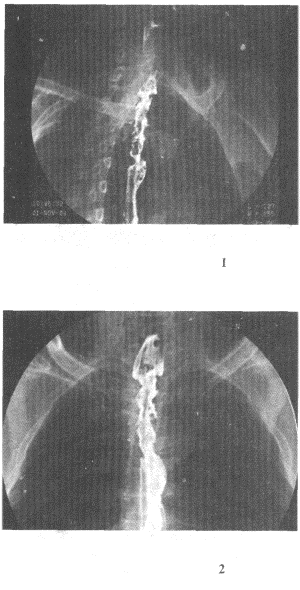

2.男,58歲,進食梗阻感,結合圖像,最可能的診斷為

正確答案:D 解題思路:食管范圍較長的不規則充盈缺損,管腔變窄,伴表面有龕影,結合病史為食管癌性病變。